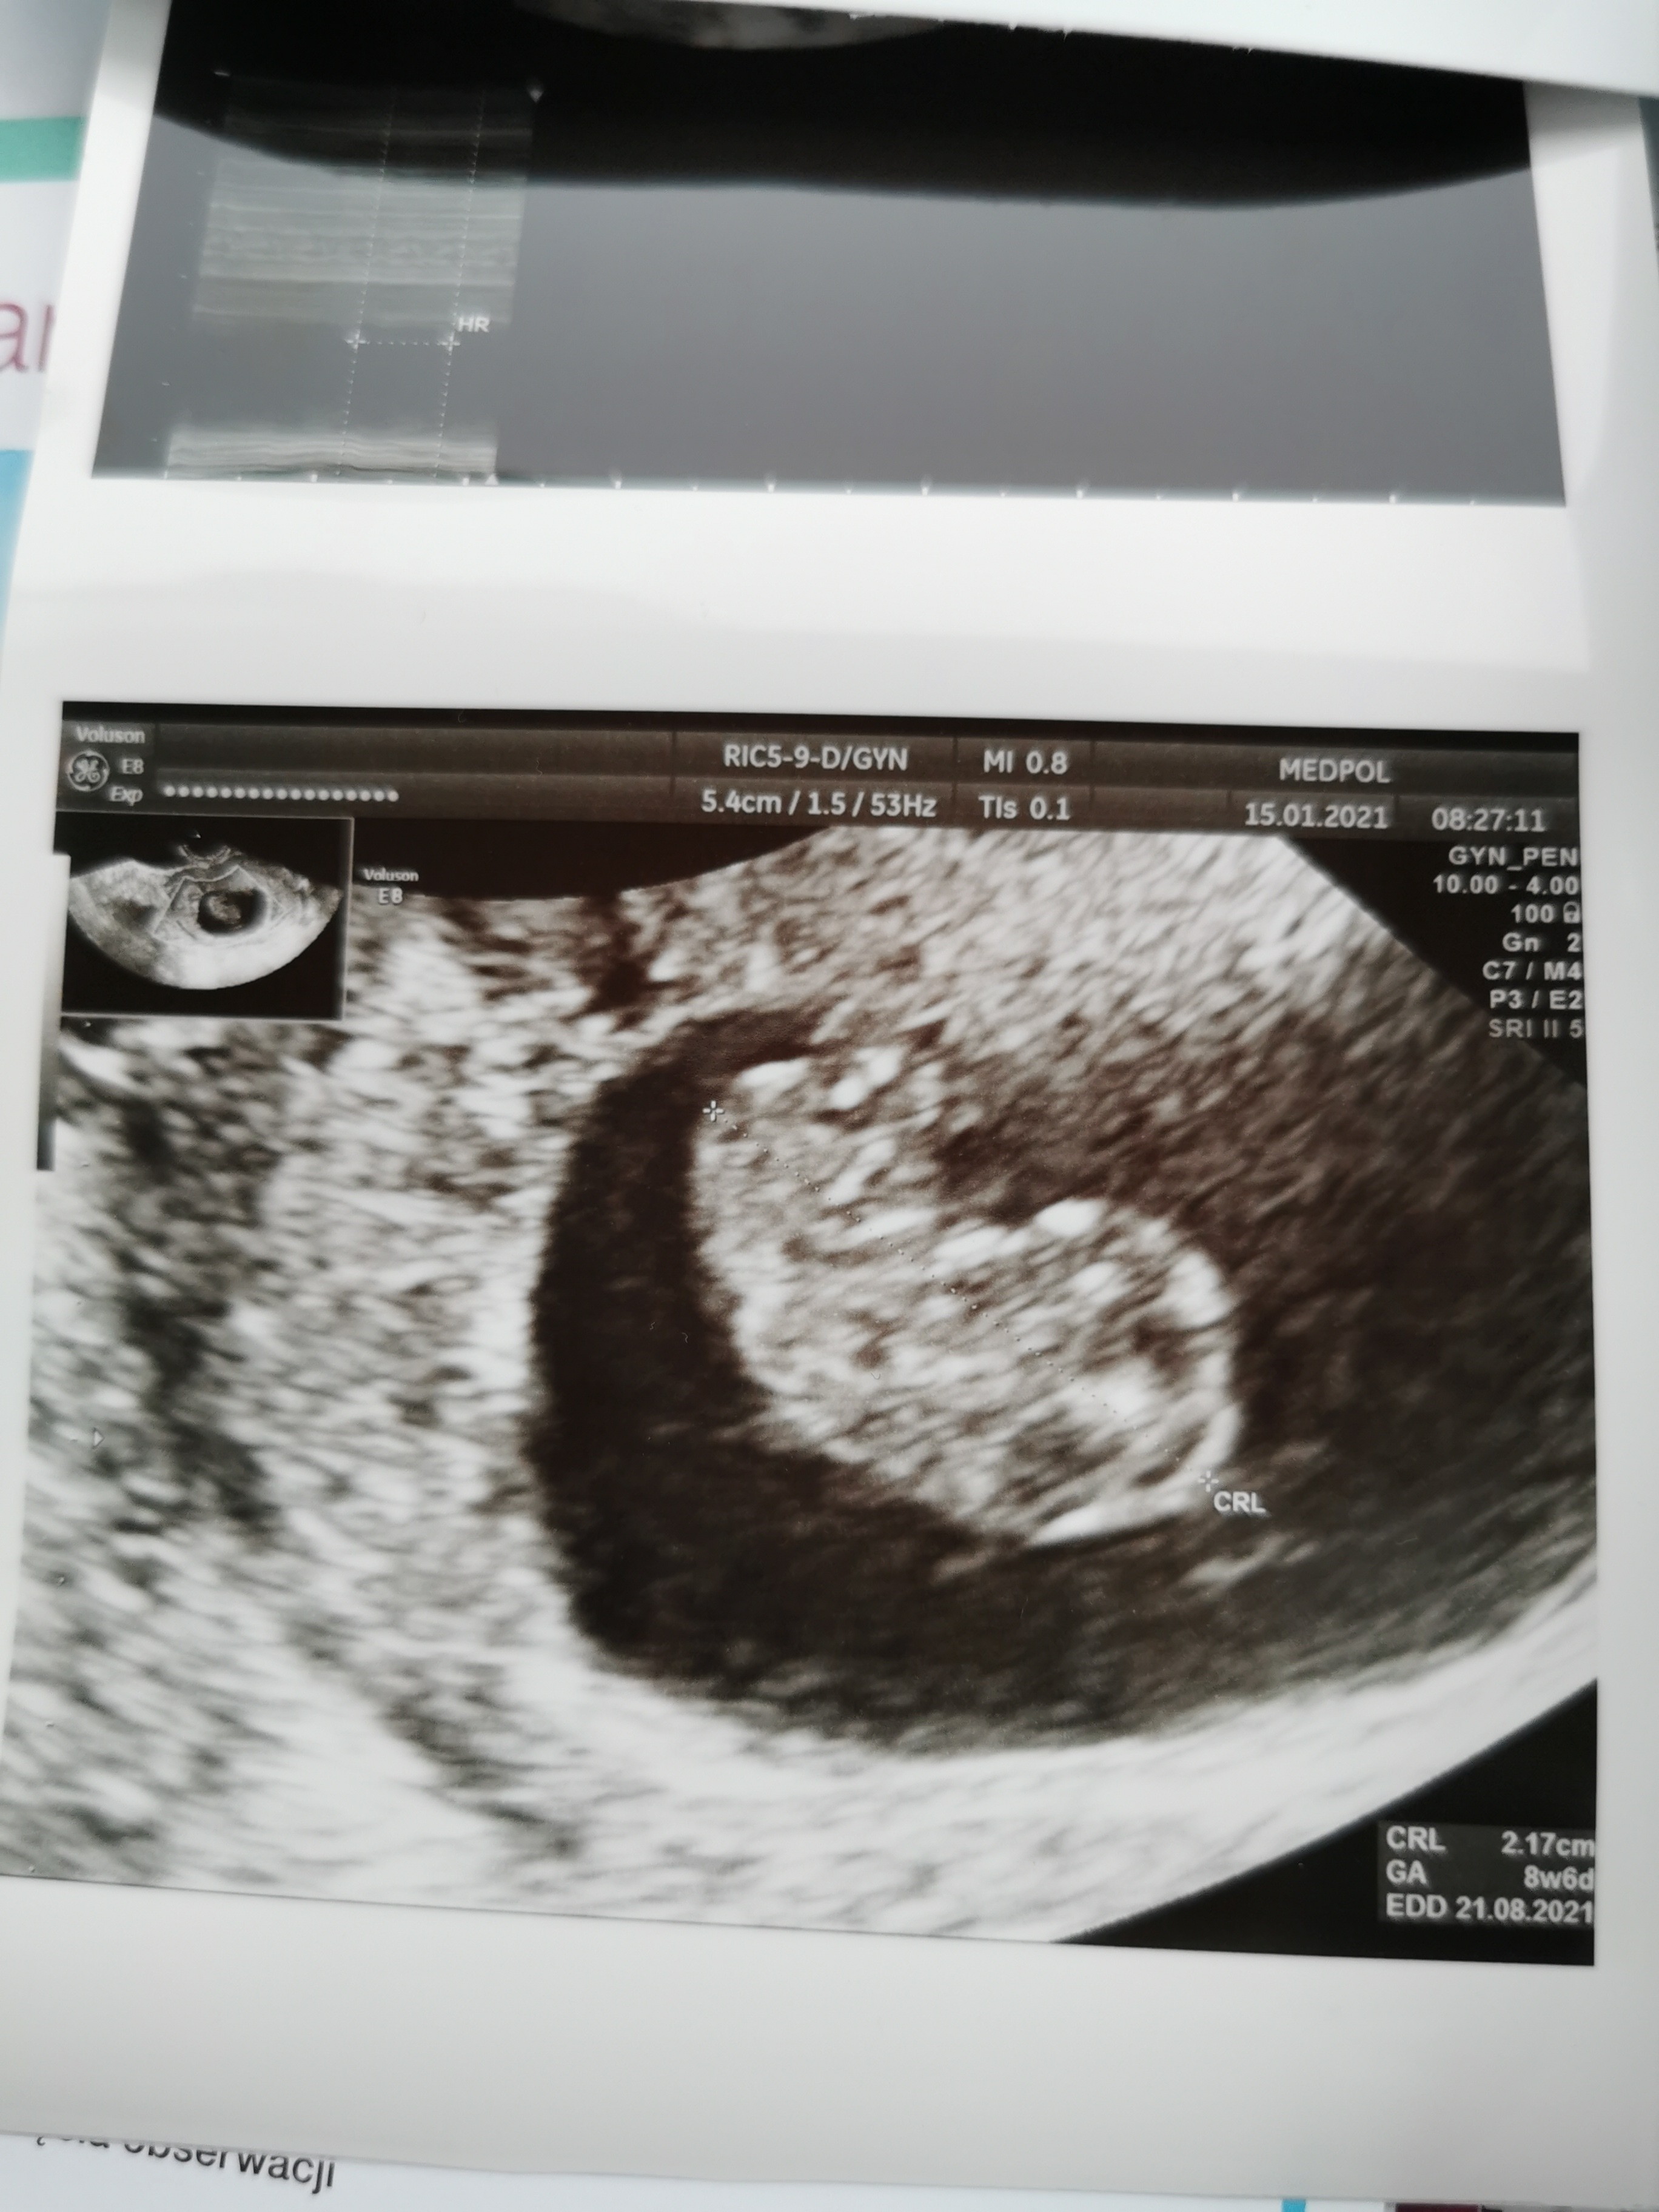

Ale fajnie mamy ten sam termin [emoji846]. Ja mam prenatalne 15.02 ciekawe czy nasze maluszki będą podobnie rosły [emoji6].Ja już po wizycie. Kropek żyje, ma się świetnie. Termin usg bez zmian na 21.08.2021.dzis 8+6.

Kropek ma 2,17cm